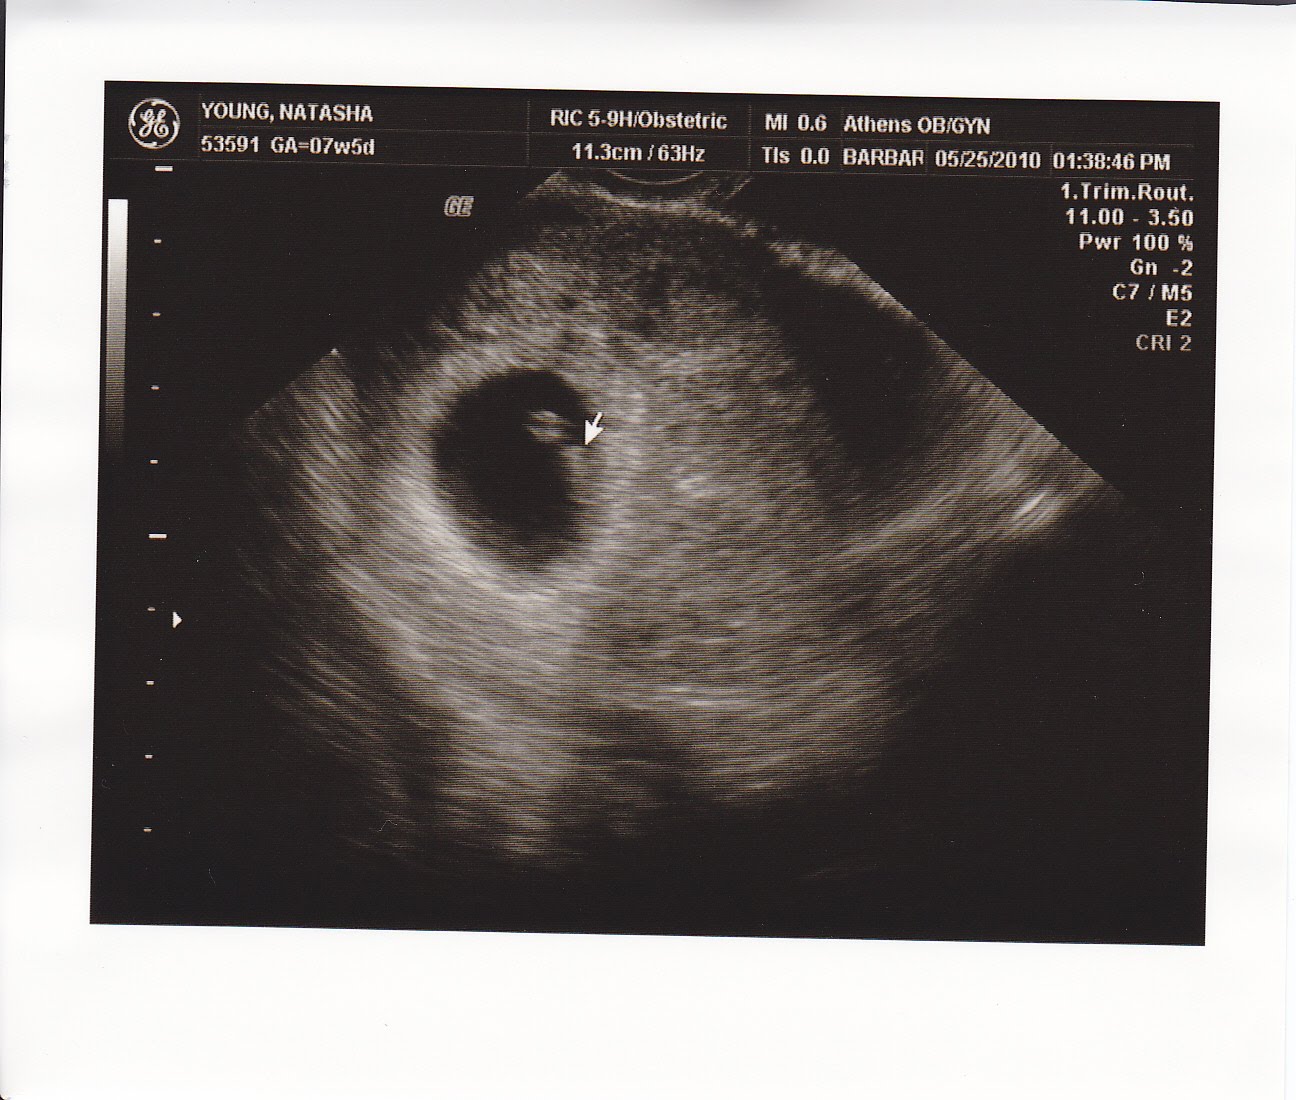

Answer (1 of 4 ): Not much! I'm not sure an abdominal ultrasound would show anything . I had a transvaginal ultrasound at 6 weeks , 5 days , and it looked like this: It shows my uterus, the dark shape in the middle . The circle there is the yolk sac . The embryo itself is too small to see in this pict . . .

At 4 weeks and 3 days , a tiny gestational sac becomes visible within the decidua . While a gestational sac is sometimes seen as early as during the 4th week of gestation, it may not be seen until the end of the 5th week , when the serum hCG levels have risen to 2500 - 3500 mIU/mL . Gestational Sac week 4 ultrasound scan

I had a scan at 5+2 and they could see a gest . sac and yolk sac, but no fetal pole . They also measured the gest . sac at 4 weeks 4 days . I was worried as miscarried before and then they had seen pretty much the same . I was sure of my LMP and that I hadn't ovulated late as I got my BFP on CD21 . However, second scan at 6+4 we saw the heartbeat .